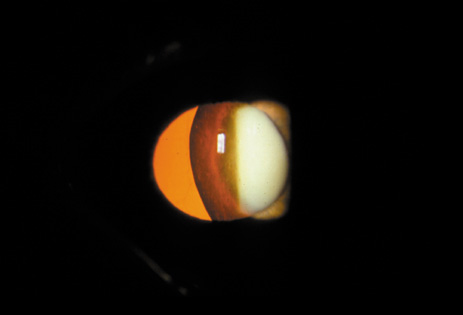

CATARACT ASSOCIATED WITH PRIMARY OCULAR DISEASES

Cataracts can occur secondary to a large number of intraocular diseases. Intraocular inflammation is the most common cause of this type of cataract. These cataracts are typically of the PSC variety. PSCs seen in retinitis pigmentosa (Fig. 31), gyrate atrophy (Fig. 32), and Usher's syndrome (Fig. 33) show finger-like projections. In persistent hyperplastic primary vitreous, the PSC is often associated with abnormal blood vessels from the hyaloid system that arborize from the posterior pole of the lens. Cataracts seen in retinal anoxia and anterior segment necrosis are thought to occur due to interference with the nutrient supplies of the lens. This leads to decreased anabolism, increased catabolism and acidity, and necrosis. The cataracts in these conditions are also of the PSC type. An acute increase in intraocular pressure can cause focal necrosis of the subcapsular epithelium and localized, fleck-like opacities (glaukomflecken). These opacities are initially located immediately under the capsule, but when new fibers are laid down they slowly become buried in the lens. Their presence indicates that the patient has experienced an acute increase in intraocular pressure. The premature occurrence of PSC and possibly nuclear-type cataracts has been noted in eyes with high myopia (Fig. 34).37–41

Fig. 33. PSC in a patient with Usher's syndrome (retinitis pigmentosa plus deafness). (Courtesy of Muriel Kaiser Kupfer, M.D.).